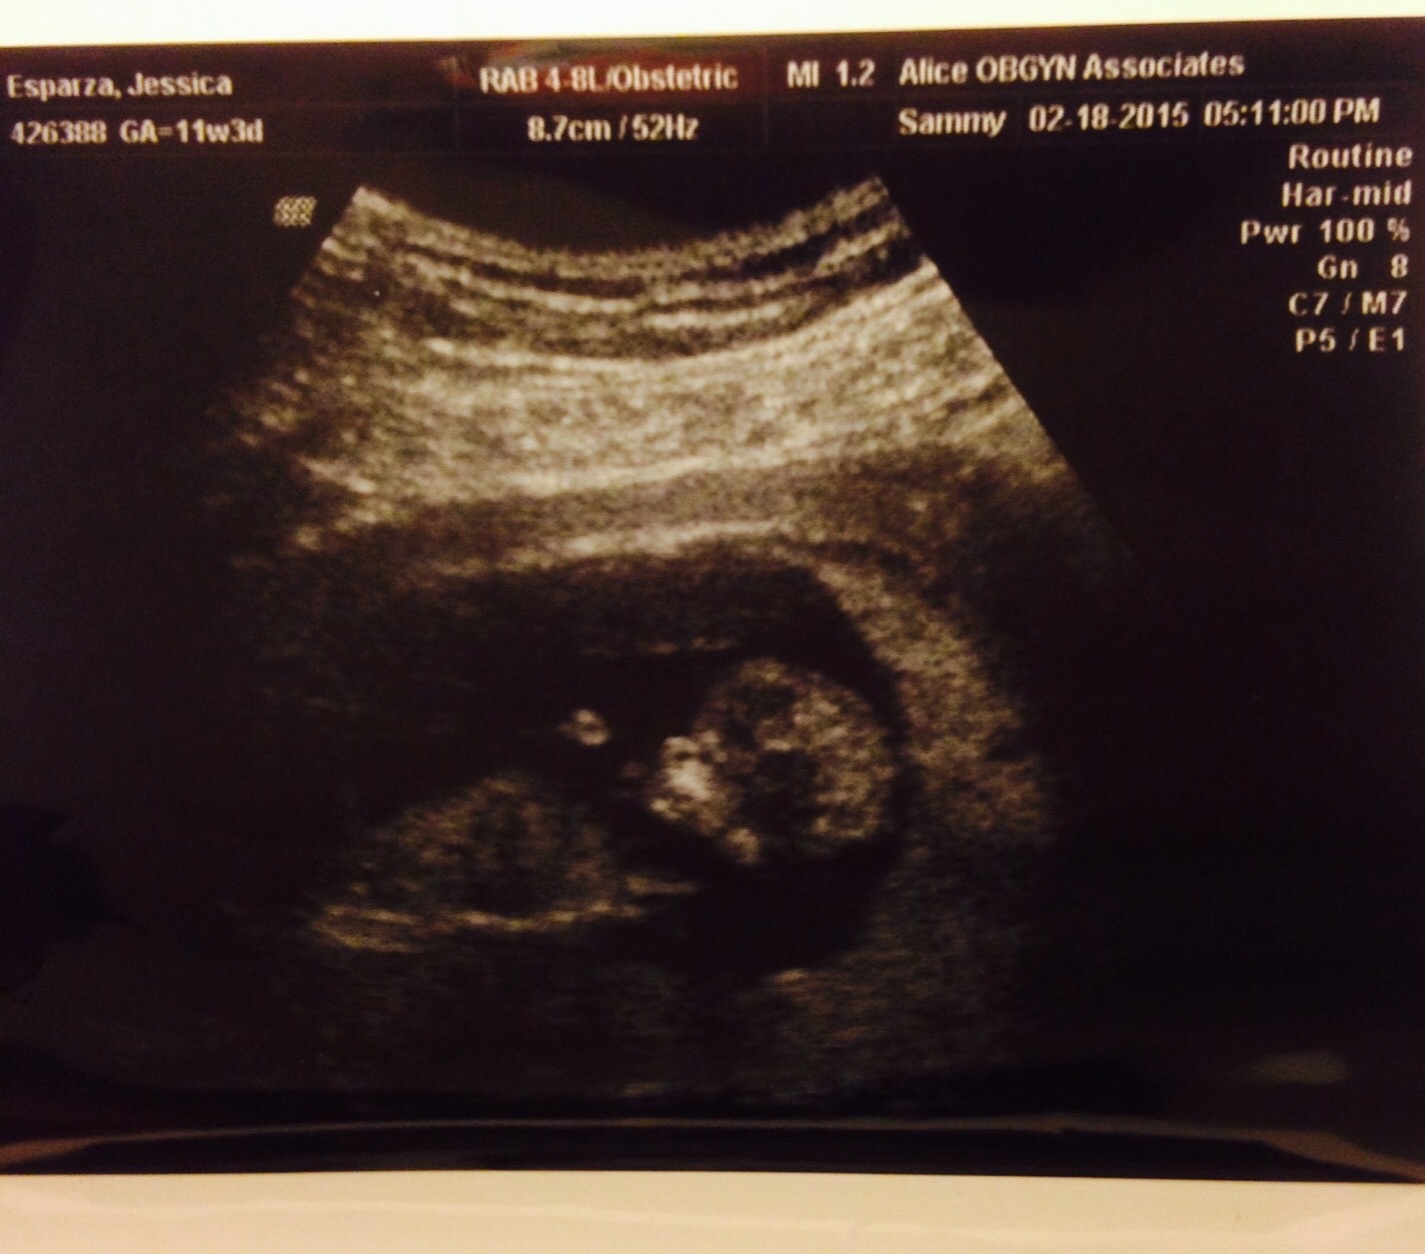

I had mine yesterday! I thought I was 12w1d but the tech said the babe was measuring between 11-12 weeks. She doesn't think they will change my due date though! So surreal seeing it flip and jump around on the screen when I couldnt feel it!